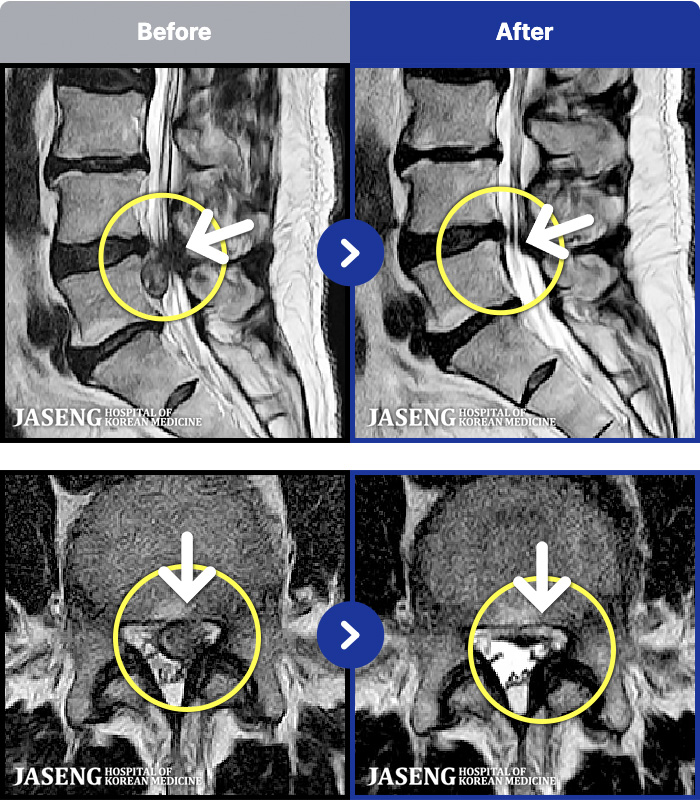

MRI ũ ʸ Ȯϼ.